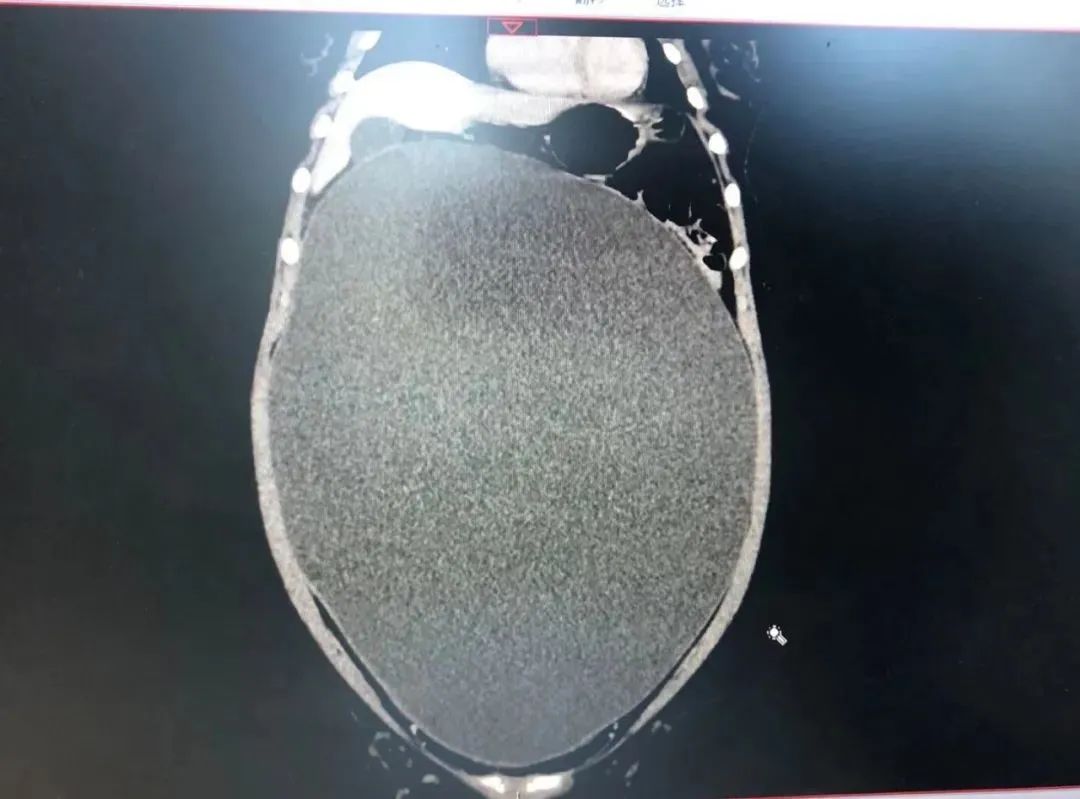

小雪的ct检查

CT检查提示,小雪并不是怀孕,肚子里的也不是什么双胞胎,而是:

超 大 卵 巢 囊 肿 !

小雪的腹腔内,有一个约40cm × 30cm × 20cm 的巨大囊肿!